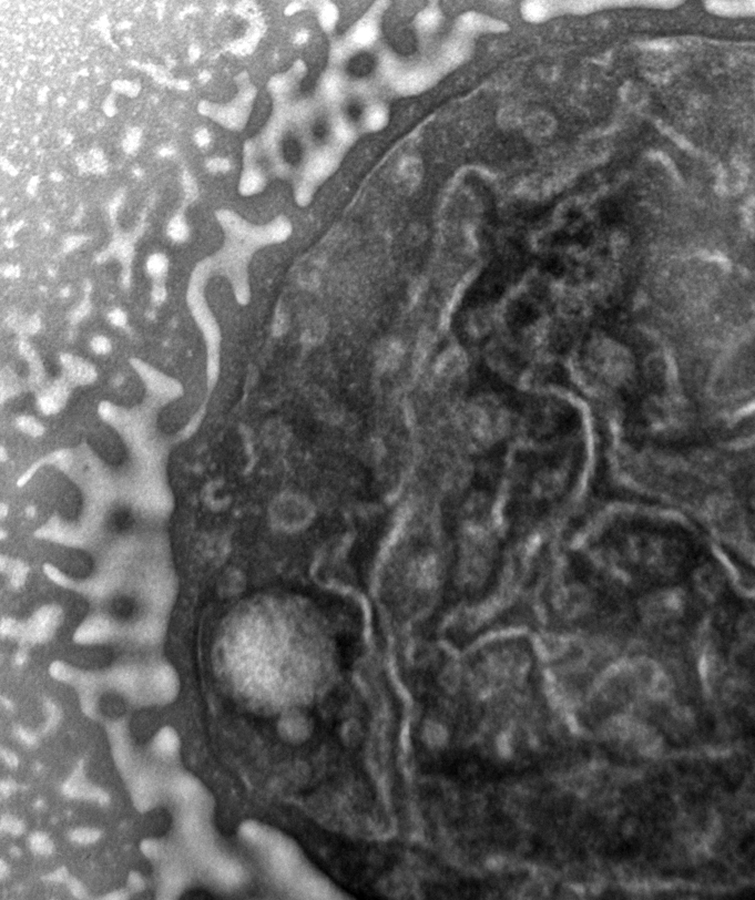

[Thanks to T.C. for the electron microscopy image of one of the strains of MRSA I was studying at the time.]